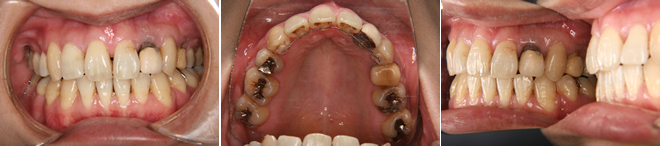

| 主訴 | 八重歯の歯肉退縮 |

| 年齢・性別 | 33歳 / 女性 |

| 治療方針 | AngleⅡ級2類の過蓋咬合。主訴の改善を第1に考え、通常あまり行わない犬歯の抜歯で対応した。 |

| 抜歯部位 | 上顎左右犬歯 |

| 使用装置 | エッジワイズ装置 |

| 治療期間 | 24か月 |

| リテーナー | 上顎インビジブル、下顎スプリングリテーナー |

| 費用 | 825,000円(税別) |